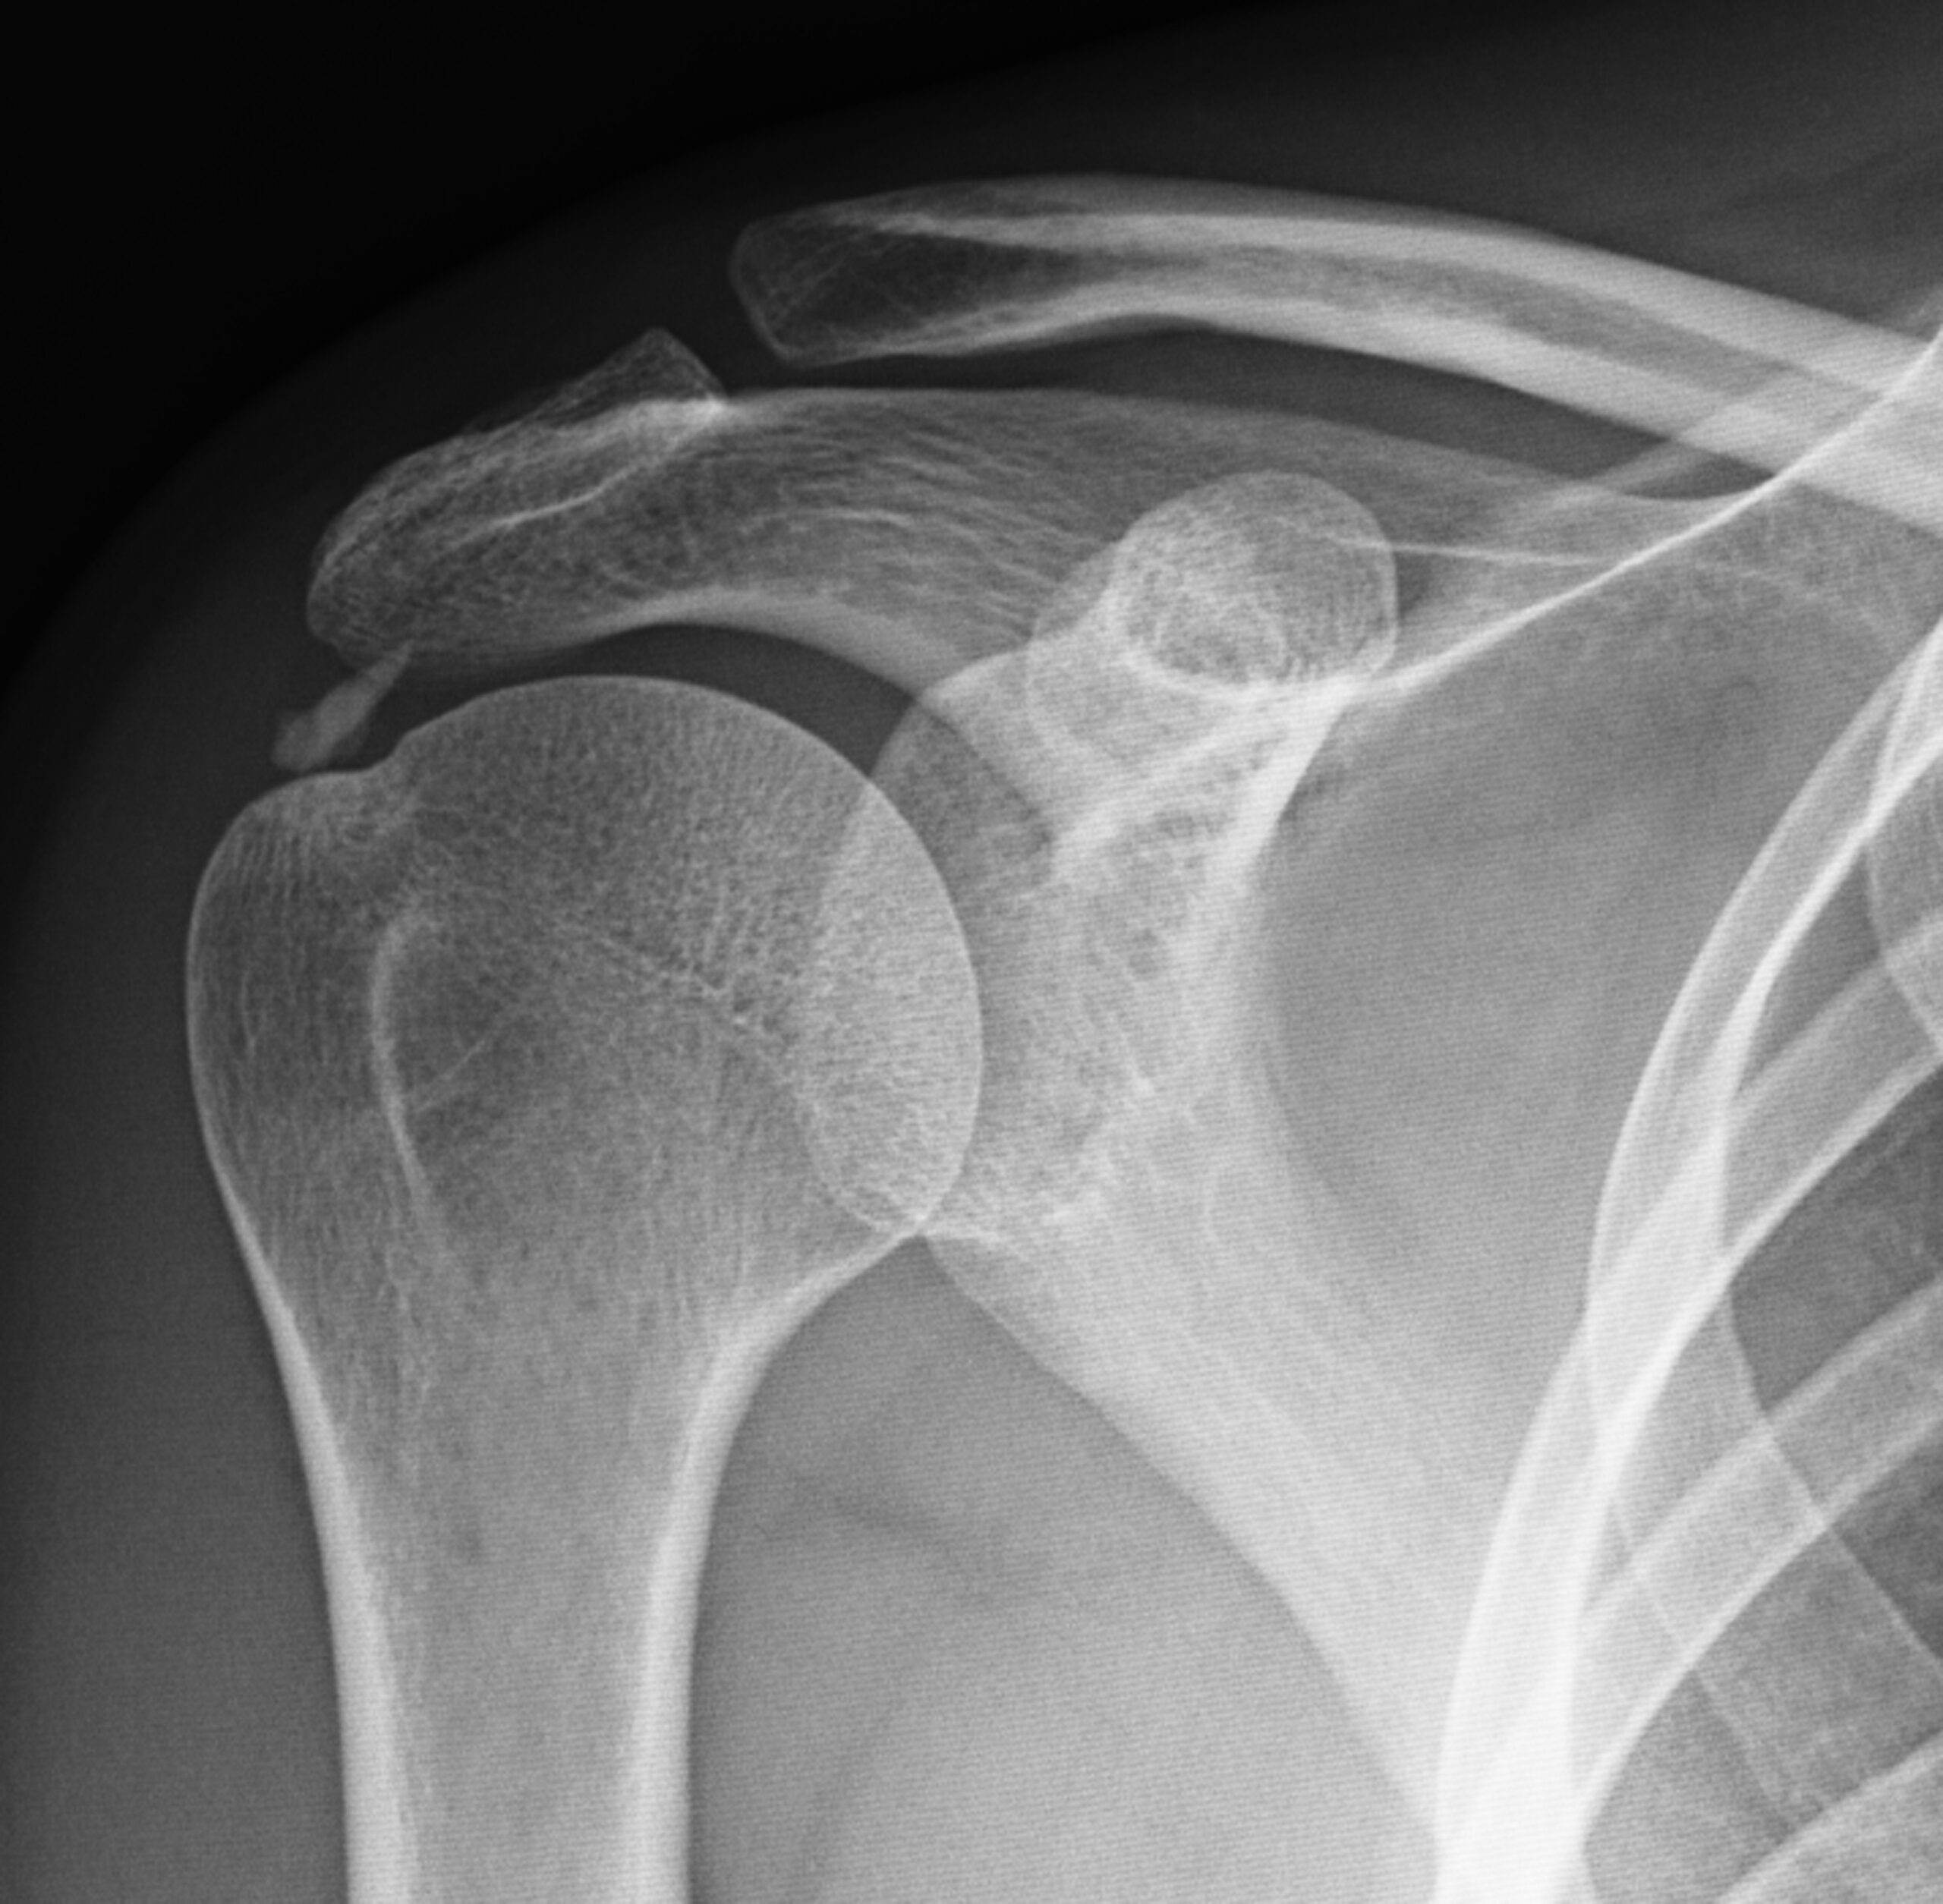

Caso 03